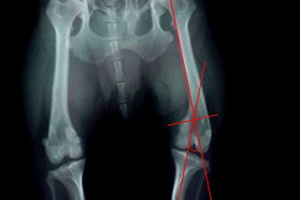

3、胫骨结节移位术

对胫骨嵴生长内旋者,将胫骨嵴移向外移动1~2公分,并用1~2枚克氏针固定。

4、截骨矫形术

如果病犬通过以上方法无效及同时膝关节严重畸形,应实施截骨矫形术,将股骨远端截断,纠正成角,使膝关节与髋关节和跗关节恢复成一条轴线上。